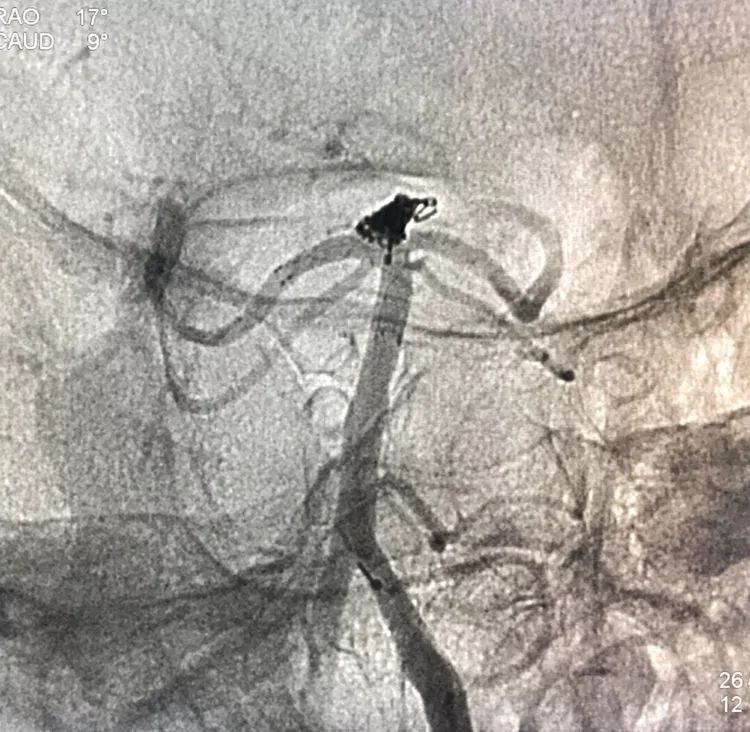

患者女性,80岁,以SAH于2017.5.20急诊入院,CTA示基底动脉顶端动脉瘤。

2.17.5.27 DSA+栓塞

左椎动脉正位造影可以看到指向左方的子瘤。

左椎动脉工作位路图

Sychro14微导丝携Headway21支架导管经左椎动脉-基底动脉进入右侧PCA,因瘤颈主要累及右侧PCA,故计划支架跨基底动脉顶端动脉瘤释放于右侧PCA-基底动脉内。